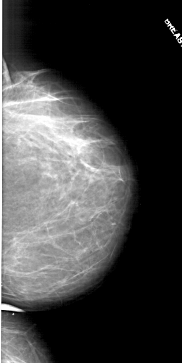

A_1711_1.RIGHT_MLO

RIGHT_MLO LINES 6346 PIXELS_PER_LINE 3061 BITS_PER_PIXEL 12 RESOLUTION 43.5 NON_OVERLAY